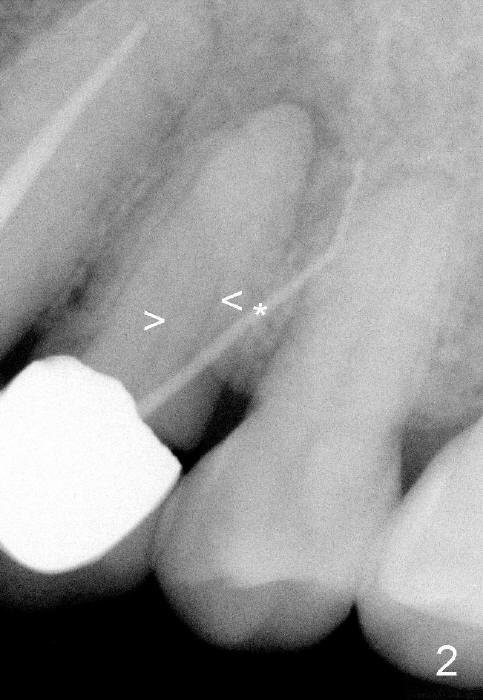

A 74-year-old man has an apical fistula (*: Gutta Percha inserted into the fistula) associated with periapical radiolucency of the tooth #12 (Fig.1 <). The first appointment fails to find the lingual canal, in spite of the fact that there are apparent two canals shown by a preop PA (Fig.2 <). Calcium Hydroxide paste is placed in the debrided buccal canal. Review of previous CT image shows the patent buccal canal (Fig.3 white <) and the apparently obliterated lingual canal (black >).